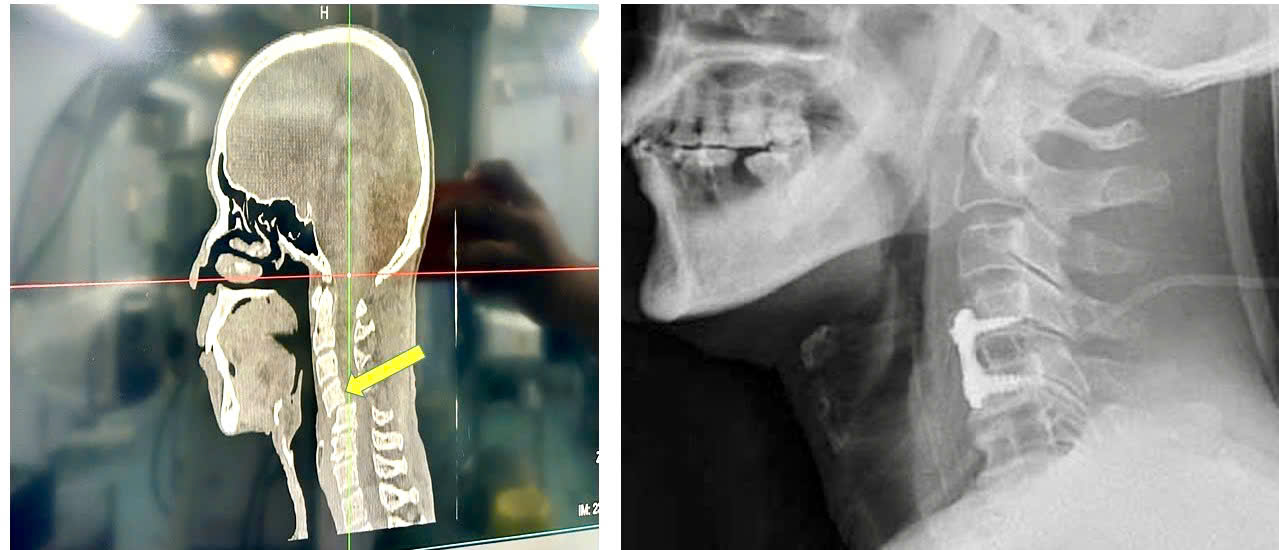

Kết quả cho thấy: Bệnh nhân bị trật đốt sống cổ C45 kèm trật cài diện khớp phía sau 2 bên. Đây là dạng tổn thương được xếp vào nhóm rất nặng và hiếm gặp, chỉ chiếm khoảng 10% các ca gãy trật cột sống cổ thấp, đa phần ở bệnh nhân nam trên 60 tuổi. Điểm đặc biệt của các trường hợp trượt và trật cài khớp 2 bên cột sống cổ là tổn thương mất vững nặng, nguy cơ liệt tủy, liệt tứ chi, rối loạn hô hấp hay tuần hoàn, chiếm đến 70-90% ngay tại hiện trường hoặc trên đường đến viện, do tủy sống bị chèn ép nặng nề và mất vững cột sống cổ.

Hình ảnh tổn thương đốt sống cổ C45 kèm trật cài diện khớp phía sau 2 bên trước và sau khi phẫu thuật được thể hiện rõ nét trên phầm mềm AI-VinDr

Sau mổ, tổn thương cột sống cổ của bệnh nhân đã được nắn trật và cố định vững hoàn toàn, không có tổn thương tuỷ, không yếu liệt và tiên lượng hồi phục hoàn toàn không có di chứng về thần kinh.